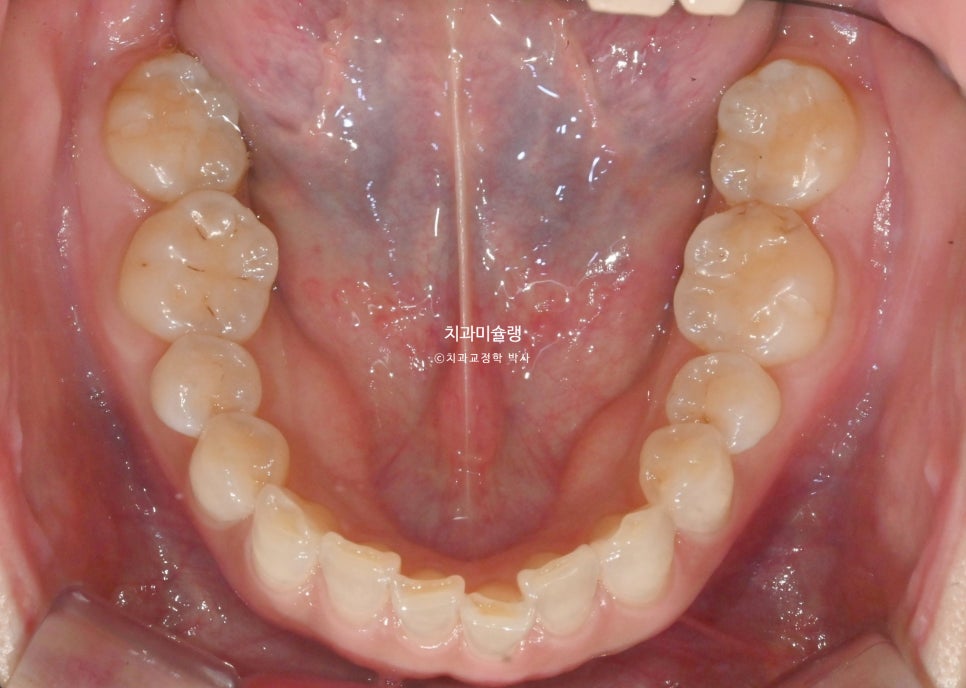

초진 시 구강 상태 분석

앞니가 삐뚤합니다.

과개교합, 인비절라인라이트로 충분하여 인비절라인라이트 권유드렸습니다. 블랙트라이앵글을 예방하기 위해 치간삭제도 소량 필요합니다.

작은어금니를 빼지 않은 비발치 교정에서는 철사 고정식 유지장치를 송곳니에서 송곳니까지 6개만 붙입니다.

하지만 앞니를 함입시켜 과개교합을 개선했기 때문에, 재발방지를 위해 유지장치를 작은어금니까지 좌우 1개씩 더 연장시킵니다.